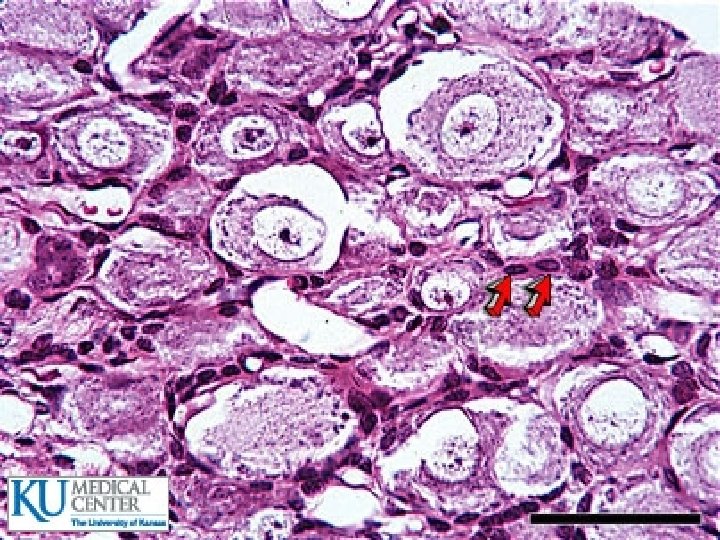

Les grandes cellules unipolaires = les neurones type I de Dogiel 70 à 80% de la population cellulaire Ø cytone de grande taille de 60 à 120µm Ø Du corps cellulaire émane une tige cytoplasmique se pelotonnant en un glomérule avant de bifurquer en deux fibres nerveuses myélinisées, l’une se dirige vers la moelle (l’axone) tandis que l’autre gagne la périphérie (dendrite). Ø

Les petites cellules unipolaires = les neurones type II de Dogiel Ø 10 à 20%. Ø cytone de petite taille de 30µm environ. Ø Ces neurones possèdent une tige cytoplasmique unique, non enroulée en glomérule qui bifurque en deux expansions, dépourvues de gaine de myéline.

Les cellules satellites Elles sont aplaties, fusiformes ou stellaires. Ces cellules sont étroitement unies au neurone ganglionnaire, elles forment une gaine continue d’épaisseur variable autour du cytone et autour de l’axone. Ces cellules de nature névroglique assurent une double fonction : Ø Une fonction trophique vis à vis du neurone. Ø Une fonction neurophagique.